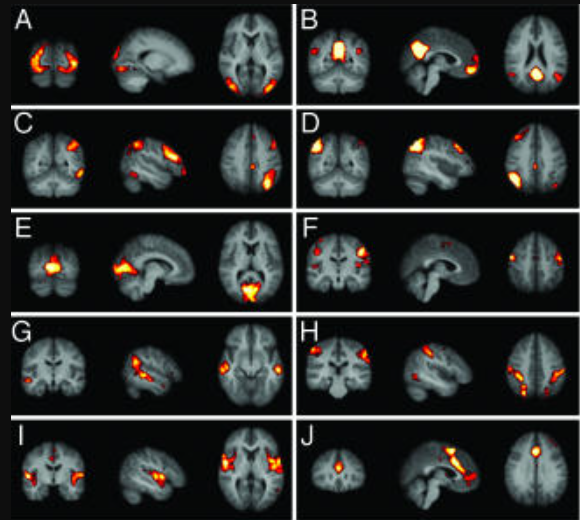

First resting state networks (De Luca)

Published in 2006 using independent components analysis

Early resting state networks De Luca 2006

Resting state networks (Damoiseaux)

Published the same year, using a different ICA method.

Early resting state networks Damoiseaux 2006